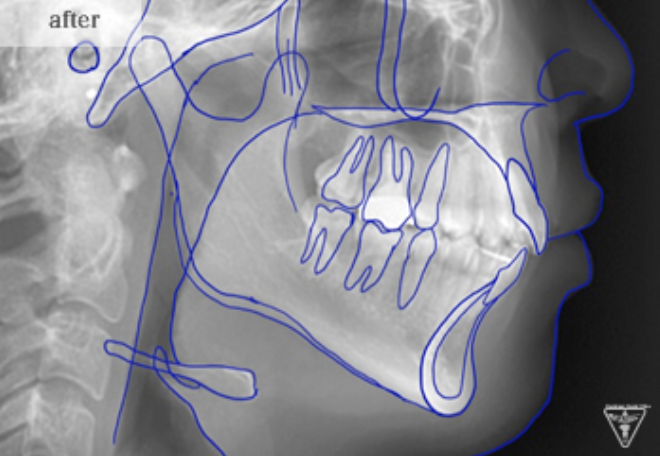

治療前

治療後